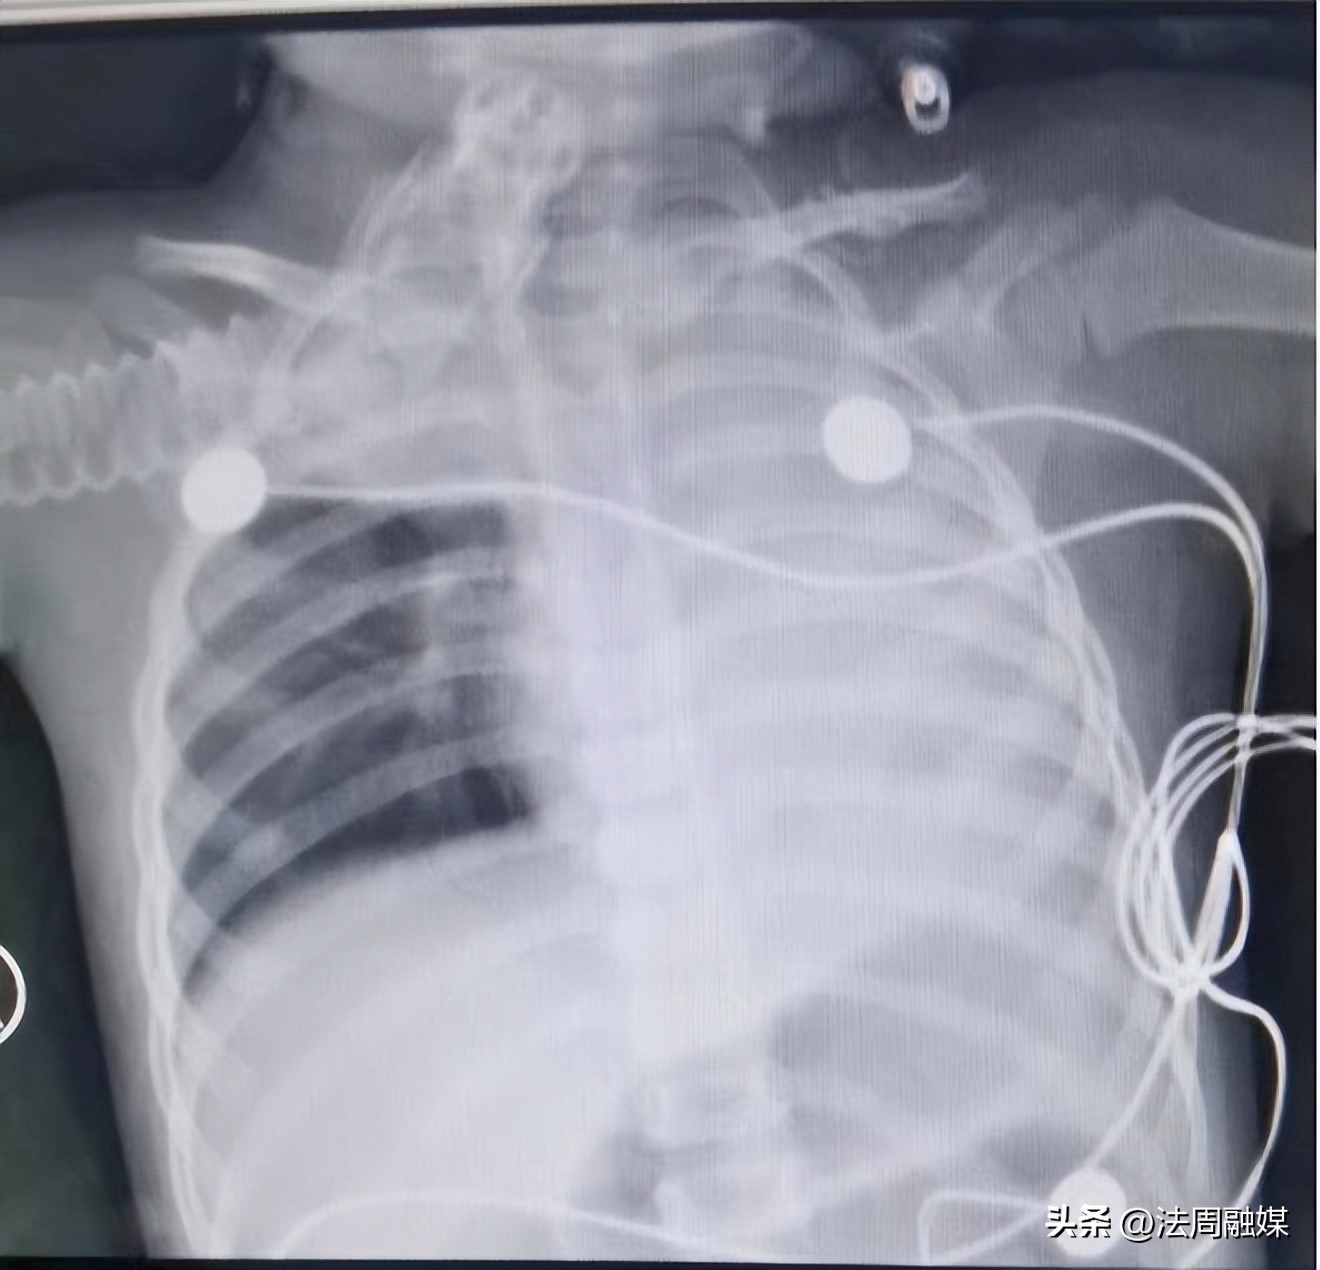

值班医生诊断考虑为支气管异物,立即联系蒋骏医生及李红艳护士床旁经气管插管行纤维支气管镜检查。患儿的左边支气管已被增生的肉芽完全堵住,右侧右中下支气管也被异物堵住,患儿的整个左肺及右边大半个肺都无法呼吸,而且由于孩子缺氧后用力吸气,已经出现负压性肺水肿。经过一夜积极救治,呼吸机参数已经调到最大值,患儿青紫症状有所缓解,但呼吸困难越发严重,二氧化碳分压已经高到测不出,出现了昏迷及脑水肿症状。

患儿术前肺水肿